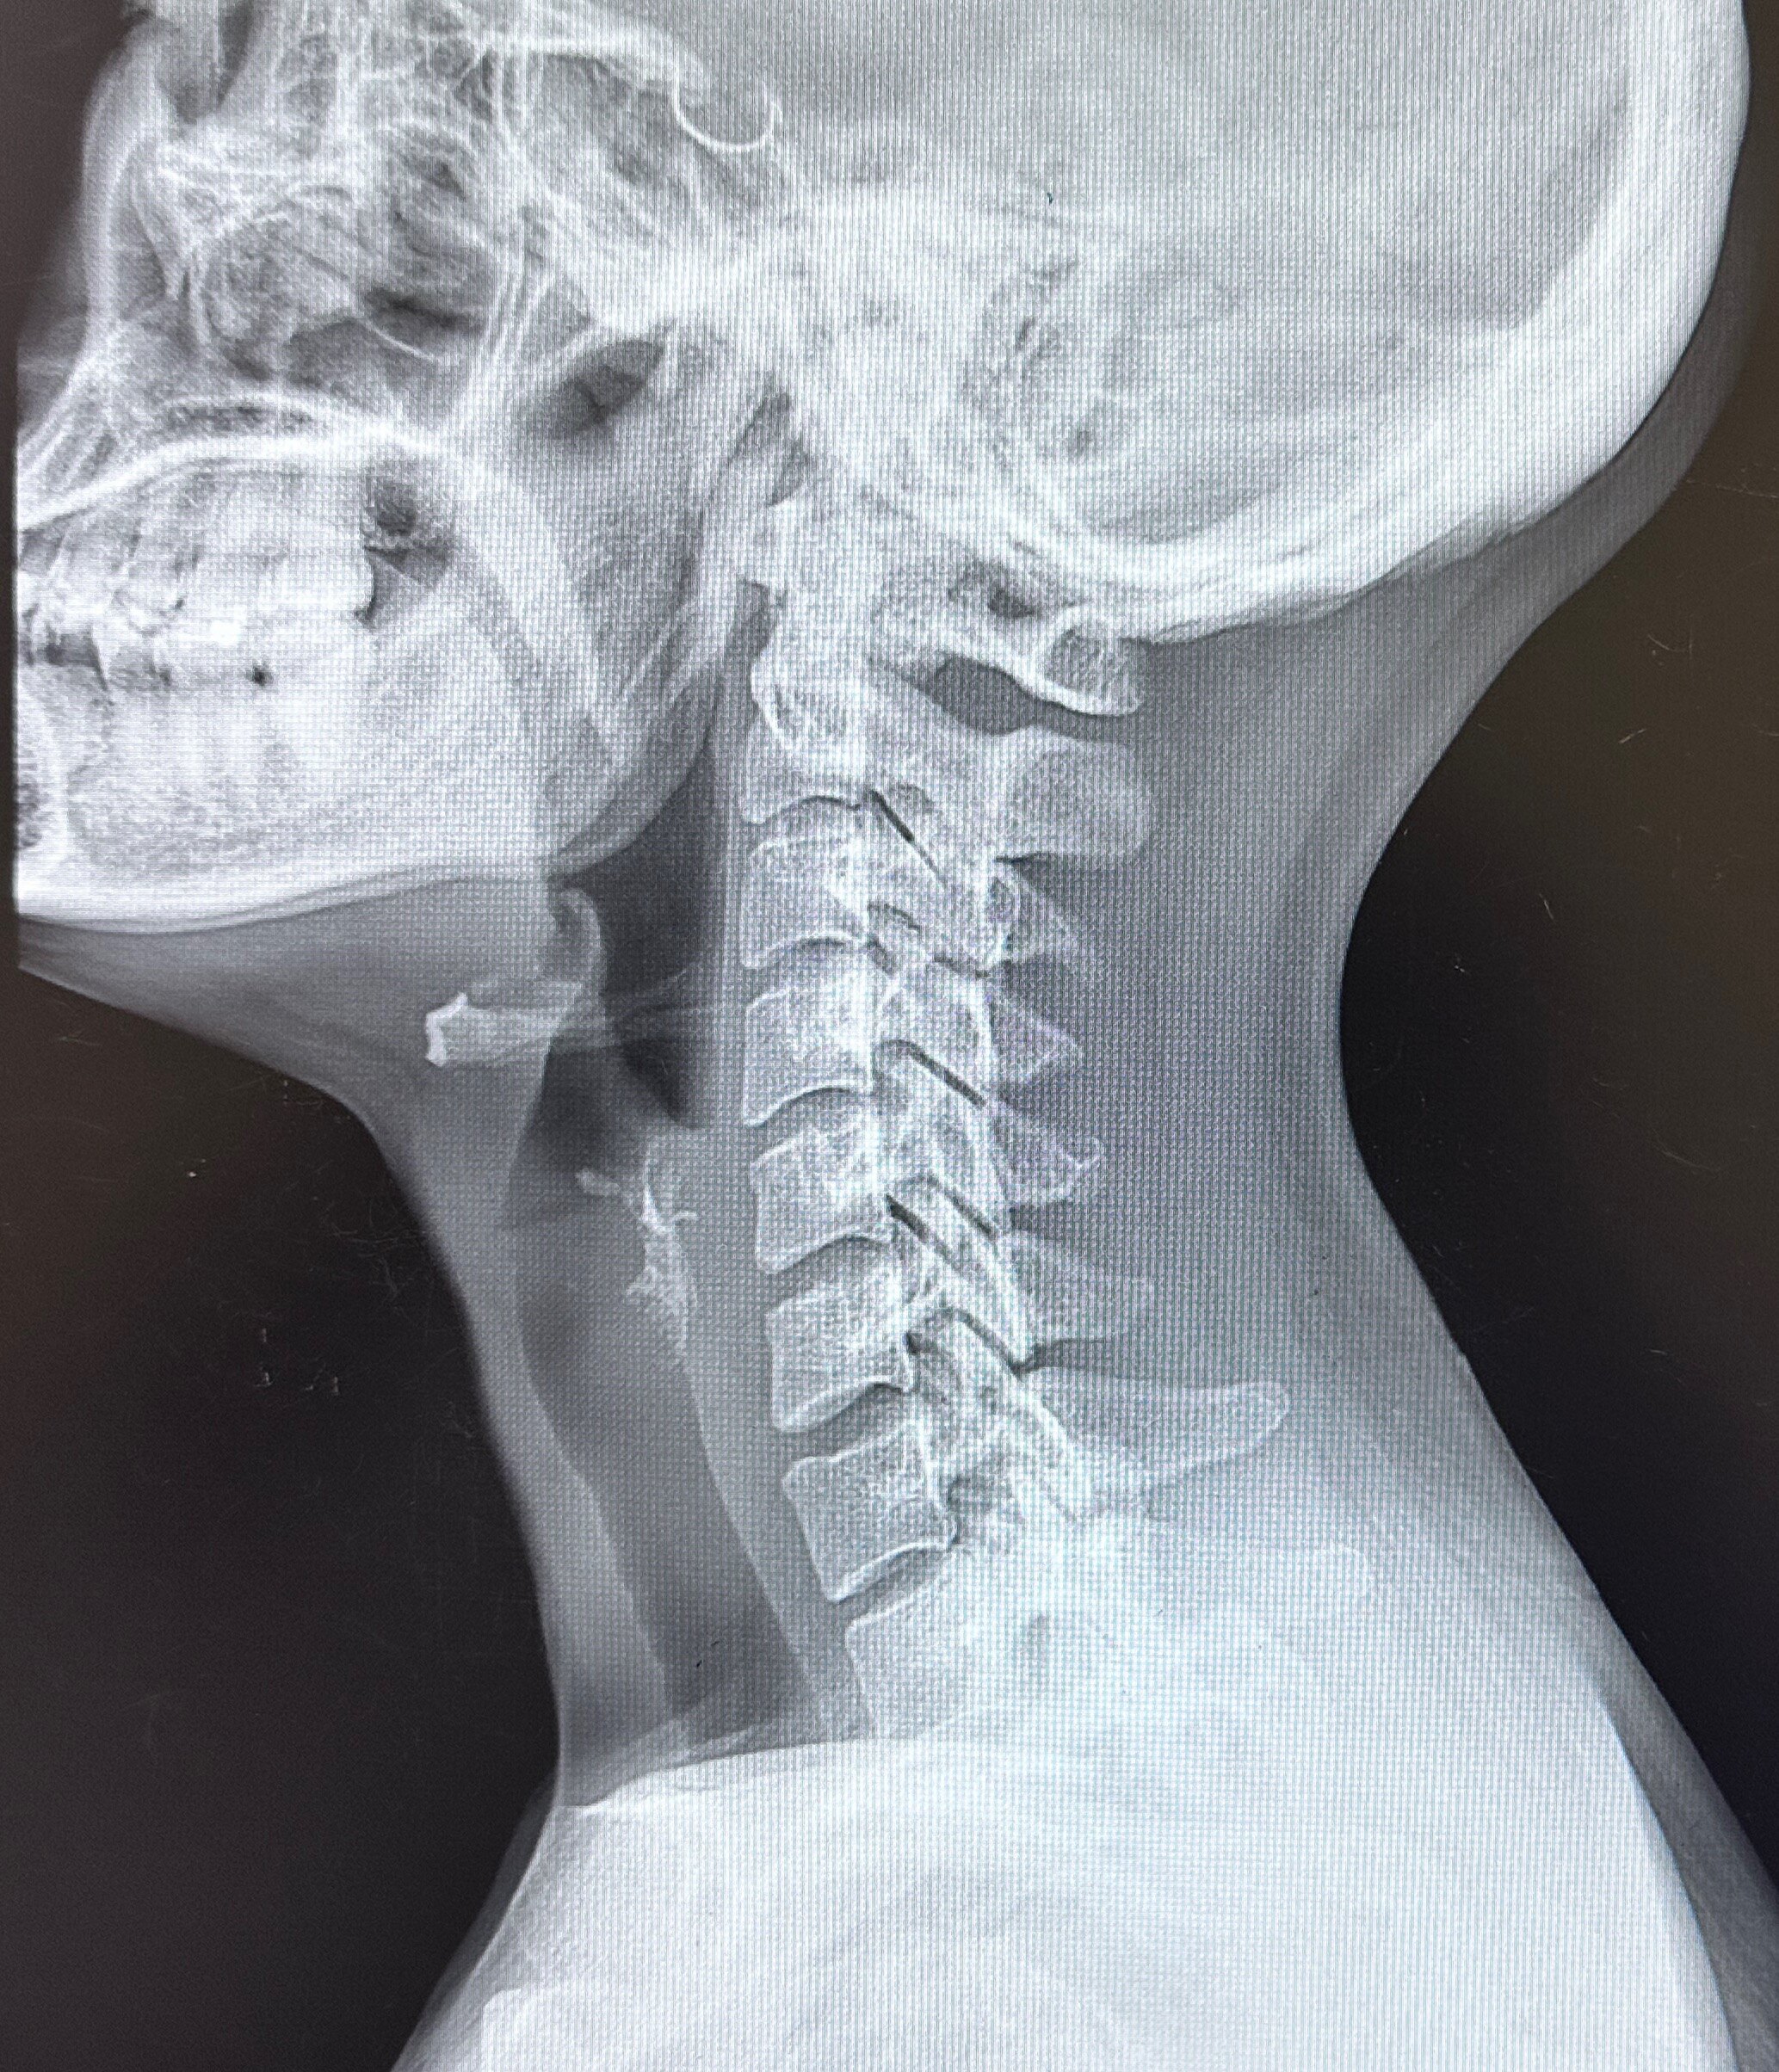

1.頸椎病急性發(fā)作期或初次發(fā)作的病人,要適當(dāng)注意休息,病情嚴(yán)重者更要臥床休息2-3周。從頸椎病的預(yù)防角度說(shuō),應(yīng)該選擇有利于病情穩(wěn)定,有利于保持脊柱平衡的床鋪為佳。2.應(yīng)調(diào)整不良的生活方式和工作習(xí)慣,比如說(shuō)在生活中避免躺在床上或趴在床上長(zhǎng)時(shí)間看手機(jī),在工作中避免長(zhǎng)時(shí)間低頭伏案,可以每隔30分鐘左右起來(lái)活動(dòng)一下,以進(jìn)行適當(dāng)?shù)恼{(diào)節(jié)。3.頸部應(yīng)放置在生理狀態(tài)下休息:一般成年人頸部墊高約10公分較好,高枕使頸部處于屈曲狀態(tài),其結(jié)果與低頭姿勢(shì)相同。側(cè)臥時(shí),枕頭要加高至頭部不出現(xiàn)側(cè)屈的高度。枕頭的位置、形狀與選料要有所選擇,也需要一個(gè)良好的睡眠體位,做到既要維持整個(gè)脊柱的生理曲度,又應(yīng)使患者感到舒適,達(dá)到使全身肌肉松弛,調(diào)整關(guān)節(jié)生理狀態(tài)的作用。4.避免頸部外傷:乘車外出應(yīng)系好安全帶并避免在車上睡覺(jué),以免急剎車時(shí)因頸部肌肉松弛而損傷頸椎。出現(xiàn)頸肩臂痛時(shí),在明確診斷并除外頸椎管狹窄后,可行輕柔按摩,避免過(guò)重的旋轉(zhuǎn)手法,以免損傷椎間盤。5.避免風(fēng)寒、潮濕:夏天注意避免風(fēng)扇、空調(diào)直接吹向頸部,出汗后不要直接吹冷風(fēng),或用冷水沖洗頭頸部,或在涼枕上睡覺(jué)。6.進(jìn)行適當(dāng)?shù)墓δ苠憻挘憻挼姆绞椒志植垮憻捄驼w鍛煉。局部鍛煉可以進(jìn)行聳肩鍛煉、雙手抱頭頸部抗阻訓(xùn)練,整體鍛煉我們推薦進(jìn)行舒緩的有氧訓(xùn)練,比如說(shuō)慢跑、太極、八段錦、游泳、跳繩等,調(diào)理頸椎及背部的同時(shí),也有利于全身氣血的調(diào)節(jié)。7.在正規(guī)醫(yī)院通過(guò)非藥物治療比如針灸推拿的方式來(lái)進(jìn)行治療。8.由專科醫(yī)生幫您安排合適的中西醫(yī)藥物治療。9.大多數(shù)頸椎病都可以通過(guò)正確的保守治療獲得效果,少數(shù)患者經(jīng)保守治療無(wú)效或確診為脊髓型頸椎病則需要及時(shí)手術(shù)才能治愈。1.頸椎病治療的前提是骨科醫(yī)生幫您明確診斷清楚,而不是自己認(rèn)為是頸椎病,因?yàn)檫€有很多其他疾病(神經(jīng)炎、結(jié)核、腫瘤、多發(fā)性硬化、感染等)也會(huì)導(dǎo)致頸椎病的癥狀,這一點(diǎn)是需要有經(jīng)驗(yàn)的專業(yè)醫(yī)生來(lái)判斷的。2.頸椎病的中醫(yī)治療雖然看似簡(jiǎn)單,但是也有風(fēng)險(xiǎn),一定要到正規(guī)醫(yī)院診治。3.太過(guò)劇烈對(duì)抗性運(yùn)動(dòng),不適于頸椎病的恢復(fù),另一方面在頸椎病疼痛或眩暈急性期也不適合做功能鍛煉,待病情穩(wěn)定之后,再進(jìn)行適當(dāng)?shù)腻憻挶容^穩(wěn)妥。4.頸椎病究竟什么時(shí)候需要手術(shù),請(qǐng)參考我的另一篇文章:您的頸椎病真的需要做手術(shù)嗎?

頸椎病的治療分為五個(gè)階梯,其中患者自己就可以做是第一和二級(jí)階梯,雖然看似簡(jiǎn)單,但是對(duì)于自身的康復(fù)非常重要,很多早期頸椎病患者只要做到這兩點(diǎn),就能徹底擺脫頸椎病的困擾。首先,得了頸椎病后首先應(yīng)調(diào)整不良的生活方式和工作習(xí)慣,比如說(shuō)在生活中避免躺在床上或趴在床上長(zhǎng)時(shí)間看手機(jī),在工作中避免長(zhǎng)時(shí)間低頭伏案,可以每隔30分鐘左右起來(lái)活動(dòng)一下,以進(jìn)行適當(dāng)?shù)恼{(diào)節(jié)。容易導(dǎo)致頸椎病的9種原因:①頸部過(guò)度負(fù)重②頭頸部外傷③高枕④側(cè)臥沙發(fā)⑤低頭看手機(jī)⑥開車⑦伏案⑧頸部受涼⑨含胸駝背。其次是進(jìn)行適當(dāng)?shù)墓δ苠憻挘憻挼姆绞椒志植垮憻捄驼w鍛煉。局部鍛煉可以進(jìn)行聳肩鍛煉、頸部抗阻訓(xùn)練,整體鍛煉我們推薦進(jìn)行舒緩的有氧訓(xùn)練,比如說(shuō)慢跑、太極、八段錦、游泳、跳繩等,調(diào)理頸椎及背部的同時(shí),也有利于全身氣血的調(diào)節(jié)。太過(guò)劇烈對(duì)抗性運(yùn)動(dòng),不適于頸椎病的恢復(fù)。第三是在正規(guī)醫(yī)院通過(guò)非藥物治療比如針灸推拿的方式來(lái)進(jìn)行治療。第四是由??漆t(yī)生幫您安排合適的中西醫(yī)藥物治療。第五是大多數(shù)頸椎病都可以通過(guò)正確的保守治療獲得效果,少數(shù)患者經(jīng)保守治療無(wú)效或確診為脊髓型頸椎病則需要及時(shí)手術(shù)才能治愈。友情提示:1.頸椎病治療的前提是骨科醫(yī)生幫您明確診斷清楚,而不是自己認(rèn)為是頸椎病,因?yàn)檫€有很多其他疾?。ㄉ窠?jīng)炎、結(jié)核、腫瘤、多發(fā)性硬化、感染等)也會(huì)導(dǎo)致頸椎病的癥狀,這一點(diǎn)是需要有經(jīng)驗(yàn)的專業(yè)醫(yī)生來(lái)判斷的。2.頸椎病的中醫(yī)治療雖然看似簡(jiǎn)單,但是也有風(fēng)險(xiǎn),一定要到正規(guī)的醫(yī)療機(jī)構(gòu)診治。